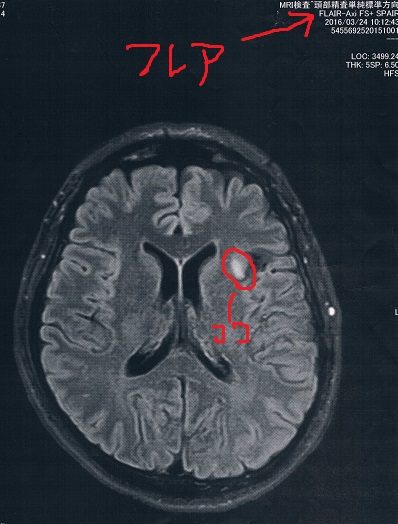

前回2016/3/24(手術後21か月)のMRI画像

今回の画像の方が、腫瘍がクッキリ写っているように見えるけど、

コントラストの違いだと思う。